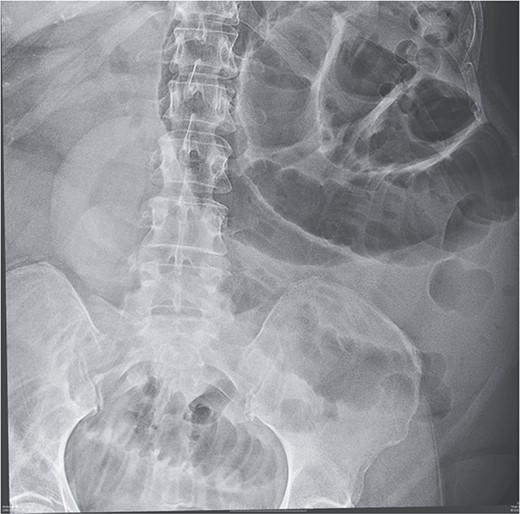

Given her abdominal symptoms and signs, she was subjected to an abdominal X-ray (Fig. 1), which showed multiple distended loops of the small bowel, and a chest X-ray, which showed left basal atelectasis. A working diagnosis of SBO was made. She was put nil by mouth. A nasogastric tube and a urinary catheter were inserted. After initial resuscitation, she was subjected to CTAP with contrast. The findings of the CTAP were in keeping with acute distal SBO secondary to an ileo-ileal intussusception. No obvious mucosal mass was stated in the initial report (Figs 2 and 3).

CT scan of abdomen: oblique coronal view of abdomen showing intussusception with low attenuation lesion distally C/W a lipoma (arrow).